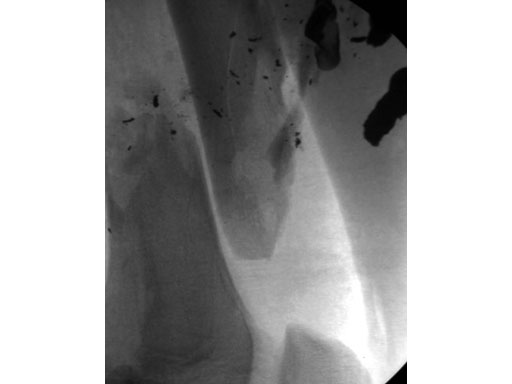

A 15-year-old male sustained an extensive soft-tissue injury with loss of bone after a gunshot (low-velocity, large caliber bullet). Neurovascular status intact, large exit wound.

The open injury (Fig 1) was debrided and cleansed. There was missing bone from the femur. Open but rapidly closing growth plates.

Fig 1 Preoperative lateral x-ray.